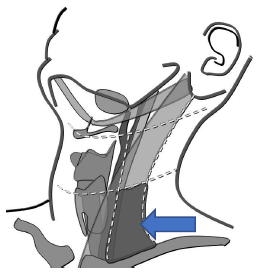

Qual o nível cervical destacado?